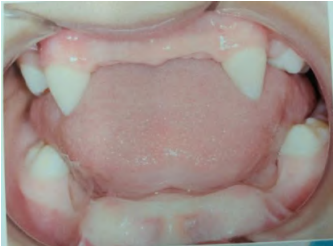

Terêncio et al., (2023) descrevem que a identificação precoce da deficiência no volume ósseo alveolar é realizada por meio de uma combinação de avaliação clínica detalhada e exames de imagem, permitindo mensurar a espessura, altura e densidade do rebordo alveolar em crianças com DE. A figura 1 demonstra algumas características dessa condição.

Figura 1 Paciente de 4 anos com ausência de dentes – Exame Clínico.

Fonte: Oliveira et al., 2024.